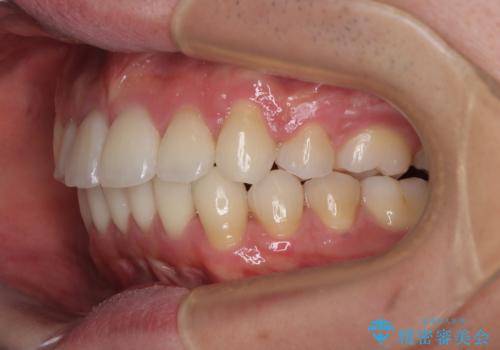

- 前歯のデコボコや八重歯を気にして来院された患者様です。

左右ともに奥歯の咬み合わせに問題があり、上顎臼歯が前方位にある状態で、結果として上顎前歯全体が前方位かつ叢生になっていました。

また、左右ともに上顎最後臼歯が頬側に転移していたため、補助装置を用いて舌側に移動をさせながら、上顎前歯を引っ込むように移動させることとしました。

口元の突出感を解消させるため上顎左右第一小臼歯2本を抜歯して、ワイヤー装置にて矯正治療を行うこととしました。

上顎のみの抜歯矯正であったため、治療期間が長期化することが予想されましたが、何とか3年弱の期間で想定通りの仕上がりで終えることができました。